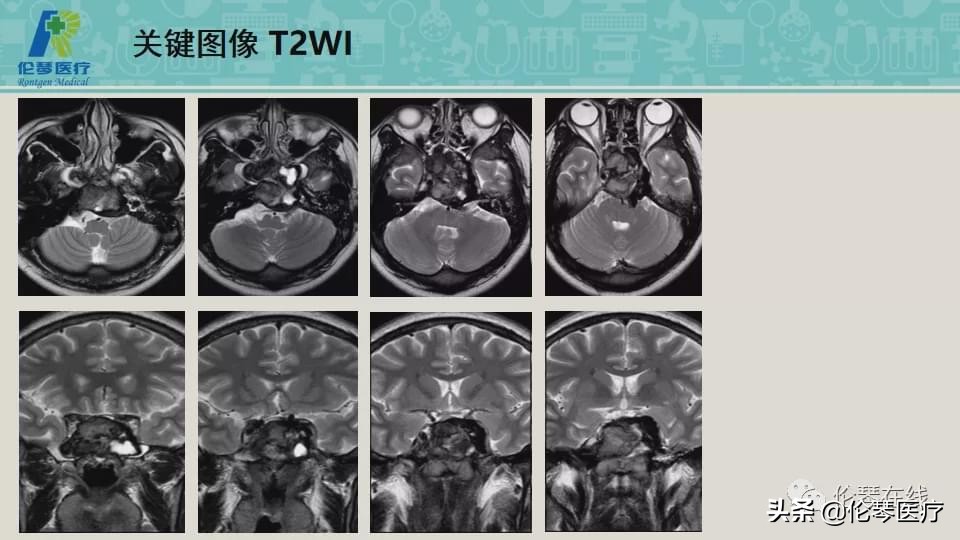

年龄:21岁

主诉:头痛,双眼内收、外展受限8个月,加重2月